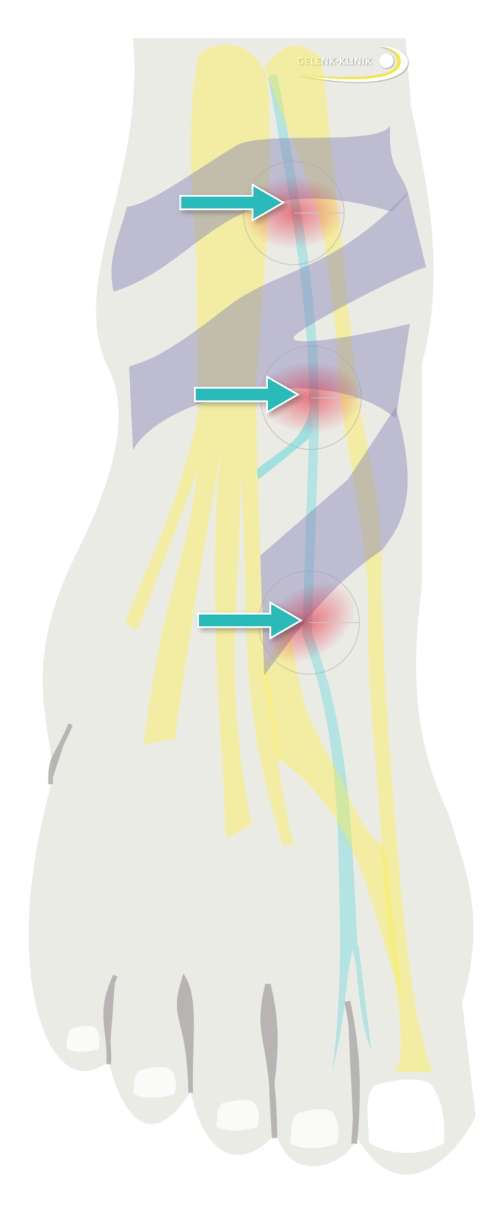

Oberflächliche Schmerzen oder Gefühlsstörungen auf dem Sprunggelenk und Fuß entstehen durch das Tarsaltunnelsyndrom. Die Nerven werden dabei gegen die oberflächlich verlaufenden Bänder gedrückt. © Dr. Thomas Schneider

Brennende oder stechende, und manchmal dumpfe Schmerzen auf der Oberfläche des Sprunggelenks resultieren häufig aus Nerveneinklemmungen. Man spricht auch von einem Nervenkompressionssyndrom. Die unter der Haut verlaufenden Nerven werden in ihrem Verlauf gequetscht oder gedrückt. Häufig sind die horizontal am Sprunggelenk verlaufenden Bänder, die den Tarsaltunnel bilden, für diese Schmerzen verantwortlich. Der Tarsaltunnel bildet eine eingeengte Durchtrittsstelle für Nerven und Blutgefäße am Sprunggelenk. Man spricht daher vom Tarsaltunnelsyndrom. Dabei bildet jedes Band eine eigene mögliche Druckstelle. Häufig entstehen diese Nervenschmerzen am Sprunggelenk nach Schwellungen im Gewebe. Verschiedene Ursachen können diese Schwellung auslösen: Wassereinlagerungen (Ödeme) können ebenso die Ursache sein wie eine Verletzung mit einer lokalen Schwellung. Neben brennenden Schmerzen begleitet häufig auch ein Taubheitsgefühl an der Fußsohle das Tarsaltunnelsyndrom.

Schematische Darstellung des Tarsaltunnels an der Außenseite des Sprunggelenks. Alle Sehnen, Nerven und Blutgefäße, die vom Unterschenkel in das Bein hineinlaufen, passieren diesen Tarsaltunnel. Eine Schwellung im Sprunggelenk führt daher zu schmerzhaften Nerveneinklemmungen. © Dr. Thomas Schneider